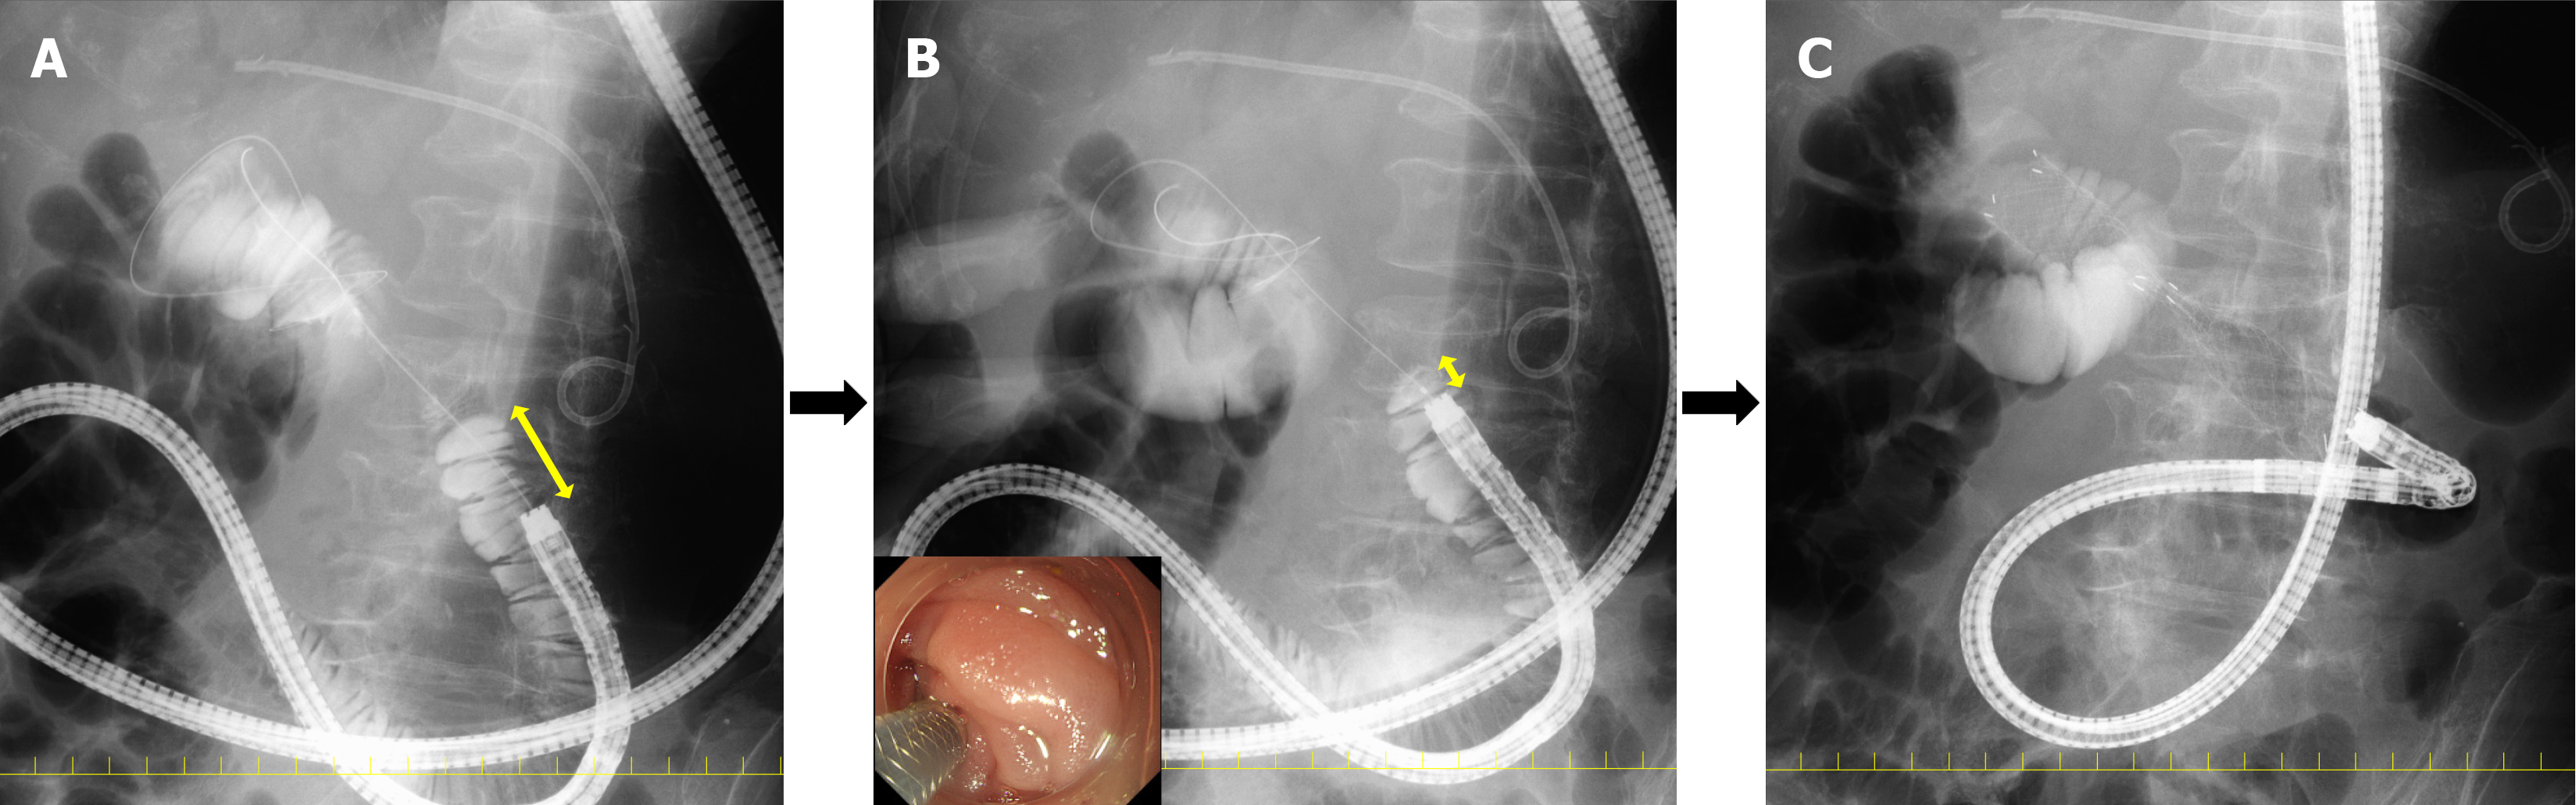

Very few reports detail the actual technique for duodenal stent placement. At our institution, we use the half-and-half technique, which we published in Digestive Endoscopy in 2024[40]. The procedure begins by advancing the endoscope towards the stricture site, injecting contrast medium through a catheter, and confirming the extent of the stricture. At this stage, a 1-2 cm gap between the proximal side of the stricture and the endoscope can facilitate a measurement (Figure 1A). Next, the endoscope is advanced closer to the stricture to enhance scope stability (Figure 1B). As the endoscope tip is positioned at the proximal side of the stricture, marking clips are unnecessary. The stent delivery system is then advanced, and the central marker is aligned with the stricture. The stent placement is initiated with approximately half of the stent remaining inside the endoscope channel; this is the half-and-half technique. The stent is partially deployed within the endoscope but not fully expanded at this stage. The stent is then fully released by simultaneously pushing out the delivery system while withdrawing the endoscope, ensuring that the stent remains in its intended position (Figure 1C). The half-and-half technique is further explained through video demonstrations in a previously published article[40].

Figure 1

Figure 1 Half-and-half technique. A: The technique begins by advancing the endoscope towards the stricture site, injecting contrast medium through a catheter, to confirm the extent of the stricture. At this stage, a 1-2 cm gap between the proximal side of the stricture and the endoscope can facilitate a measurement; B: The endoscope is advanced closer to the stricture to enhance scope stability. Since the endoscope tip is positioned at the proximal side of the stricture, marking clips are unnecessary; C: The stent delivery system is then advanced, and the central marker is aligned with the stricture. The stent placement is initiated with approximately half of the stent remaining inside the endoscope channel. The stent is partially deployed within the endoscope but is not fully expanded at this stage. The stent is then fully released by simultaneously pushing out the delivery system while withdrawing the endoscope, ensuring that the stent remains in its intended position.

This half-and-half technique allows for stable endoscope positioning while utilizing the working channel to deploy the stent, effectively preventing stent jumping. The technique also facilitates accurate stent placement even in challenging situations, such as during stent deployment using a balloon-assisted enteroscope.